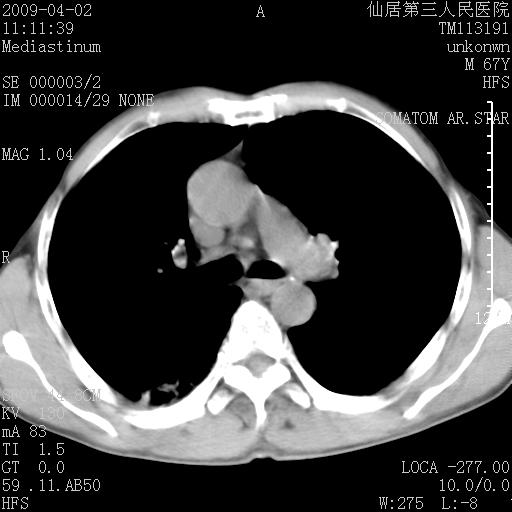

患者老年男性,乏力畏寒来诊,摄胸片示右下肺感染性病变,抗炎两周后复查胸片,无好转有进展。

后做ct平扫表现如下:

病灶呈蜂窝征,纵隔多个淋巴结肿大;肺泡癌需考虑

我认为普通的感染应该可以除外,间质性肺炎可能性较大,但如何解释纵膈的淋巴结肿大呢

考虑双肺间质性改变(间质纤维化?)伴右肺下叶感染。